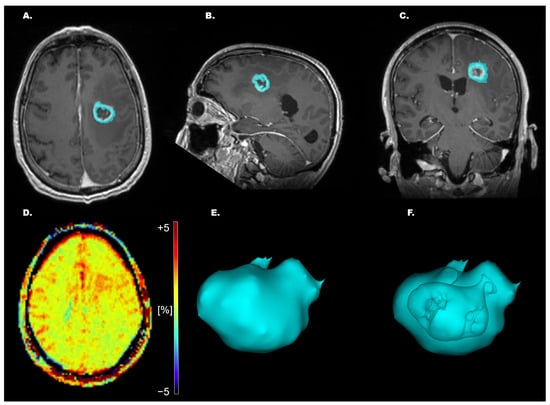

These non-tumoral portions were removed from the ROI in 3D Slicer so that only viable, enhancing tumor tissue remained for APTw quantification (Figure 1). Mean, median, and maximum (max) APTw% signals were then extracted from the segmented pathological tissue.

Figure 1. Example of whole-tumor segmentation for a high-grade glioma (HGG), with corresponding 3D rendering. (AC) T1-MPRAGE Gd-enhanced axial/sagittal/coronal plane. (D) APTw image showing hotspots of increased APTw% signal from −5 to +5%. (E) 3D rendering of entire segmentation. (F) 3D rendering of entire segmentation with depiction of excluded central necrotic, cystic, or hemorrhagic areas.

The primary aim of this study was to assess the capability of APTw imaging in differentiating high-grade glial tumors based on their p53/ATRX/IDH/Ki-67 index/MGMTp methylation status. We showed that APTw measurements obtained from the manual segmentation of enhancing solid tumor (Figure 1) have the potential to non-invasively differentiate HGGs based on their p53 status. In the present study, the non-methylated MGMTp HGG exhibited a significantly higher max APTw% signal vs. methylated tumors in the 42 HGG cases according to WHO 2016 classification including the six IDH-mutated cases, but this finding did not reach significance when re-analyzed to include only the 36 IDHwt glioblastoma patients according to the WHO CNS5/2021 classification (Table S2). HGGs with normal p53 expression showed significantly higher mean, median, and mean + median APTw% signals vs. HGGs with overexpressed p53, both in the GBM cohort according to WHO 2016 classification and the present WHO CNS5/2021 (Tables S2 and S4).